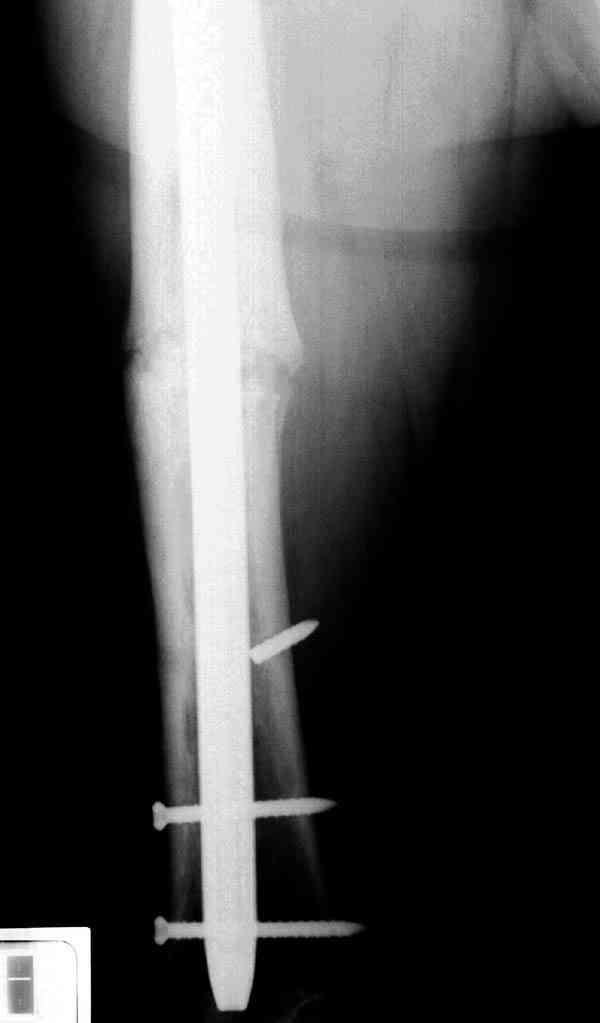

Сросшаяся малоберцовая как распорка привела к образованию ложного сустава. В таких случаях удаляем сломанный штифт и проводим стимуляцию ложного сустава рассверливанием. Рассверливание канала создает стимуляцию на месте ложного сустава, и динамический вариант блокировки штифта с большим диаметром создаст стабильность. Ранняя нагрузка после остеотомии малоберцовой приведет к сращению ложного сустава.

Приспособление для удаления сломанных штифтов и наличие ЭОП облегчит задачу. При отсутствии крючка тогда можно применить обычный длинный ball pointed guide wire от интрамедулярного набора. Проволока, пропущенная за пределы гвоздя и зажатая другая вытащат сломанный конец штифта без проблем.